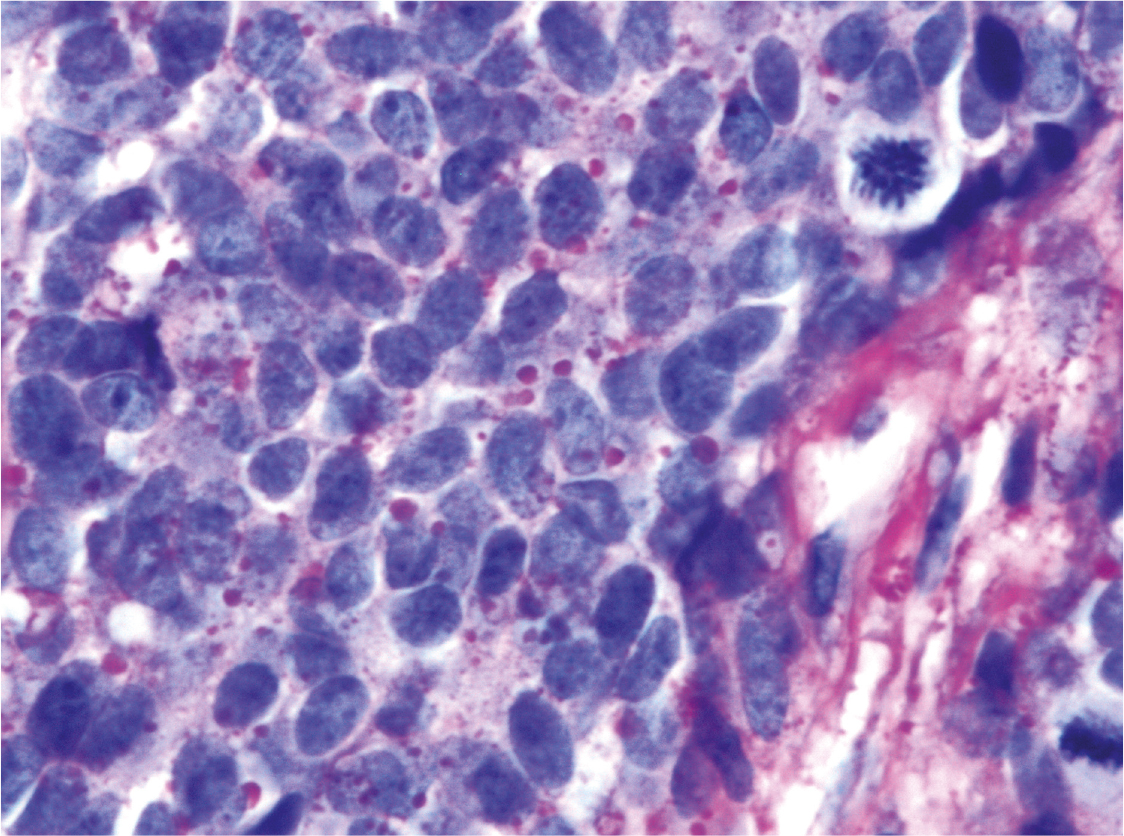

Fig 2

Figure 2. Glycogen deposits in ES/PNET. The microphotograph shows a high power view of the Ewing sarcoma/Primitive neuroectodermal tumor (ES/PNET) depicted in figure 1 with particulate of glycogen in the cytoplasm of the tumor cells and a high nucleus to cytoplasm ratio. Two mitoses (right upper corner and right lower corner) are also seen (Periodic acid Schiff staining x 630 original magnification).